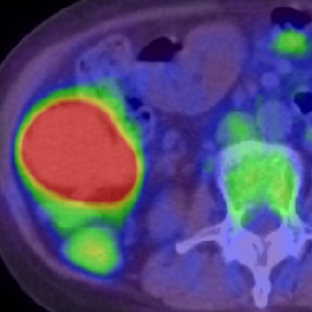

a. PET MIP像

b. PET/CT像

c. CT像、化学療法後

d. PET MIP像

e. PET/CT像

f. CT像

図2 悪性リンパ腫治療効果判定:完全寛解 化学療法前